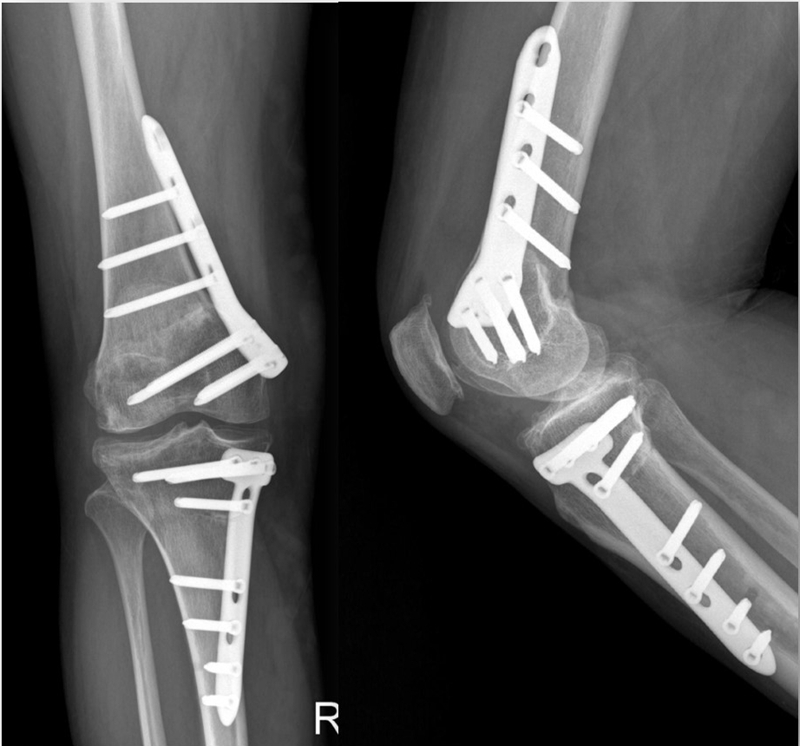

术后影像

患者二,女性,膝外翻,膝外侧疼痛。通过做畸形分析后发现,该患者同时存在股骨侧畸形、胫骨侧畸形和关节内畸形(LDFA=82°,MPTA=104°,JLCA=6°)。

对于这类病人如何进行术前设计的关键点就在于目标力线应如何设计。要在骨性截骨的时候纠正骨性畸形,关节内畸形要通过关节内的方法解决。因为JLCA不平行,所以要同时画股骨侧关节线和胫骨侧关节线,并垂直于股骨侧关节线做出股骨侧目标力线,垂直于胫骨侧关节线做出胫骨侧目标力线。

根据各自目标力线,分别计算股骨内侧闭合和胫骨内侧闭合角度。

此患者股骨内侧闭合6°,经股内侧闭合13°。